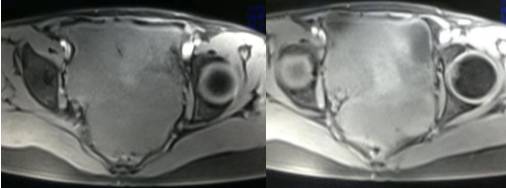

女性,42岁。

主诉:下腹部胀痛不适1月余

病史:自诉13岁时患“结核”,8年前行“左侧附件包块”切除术。

MR检查:

病理结果:黄体血肿